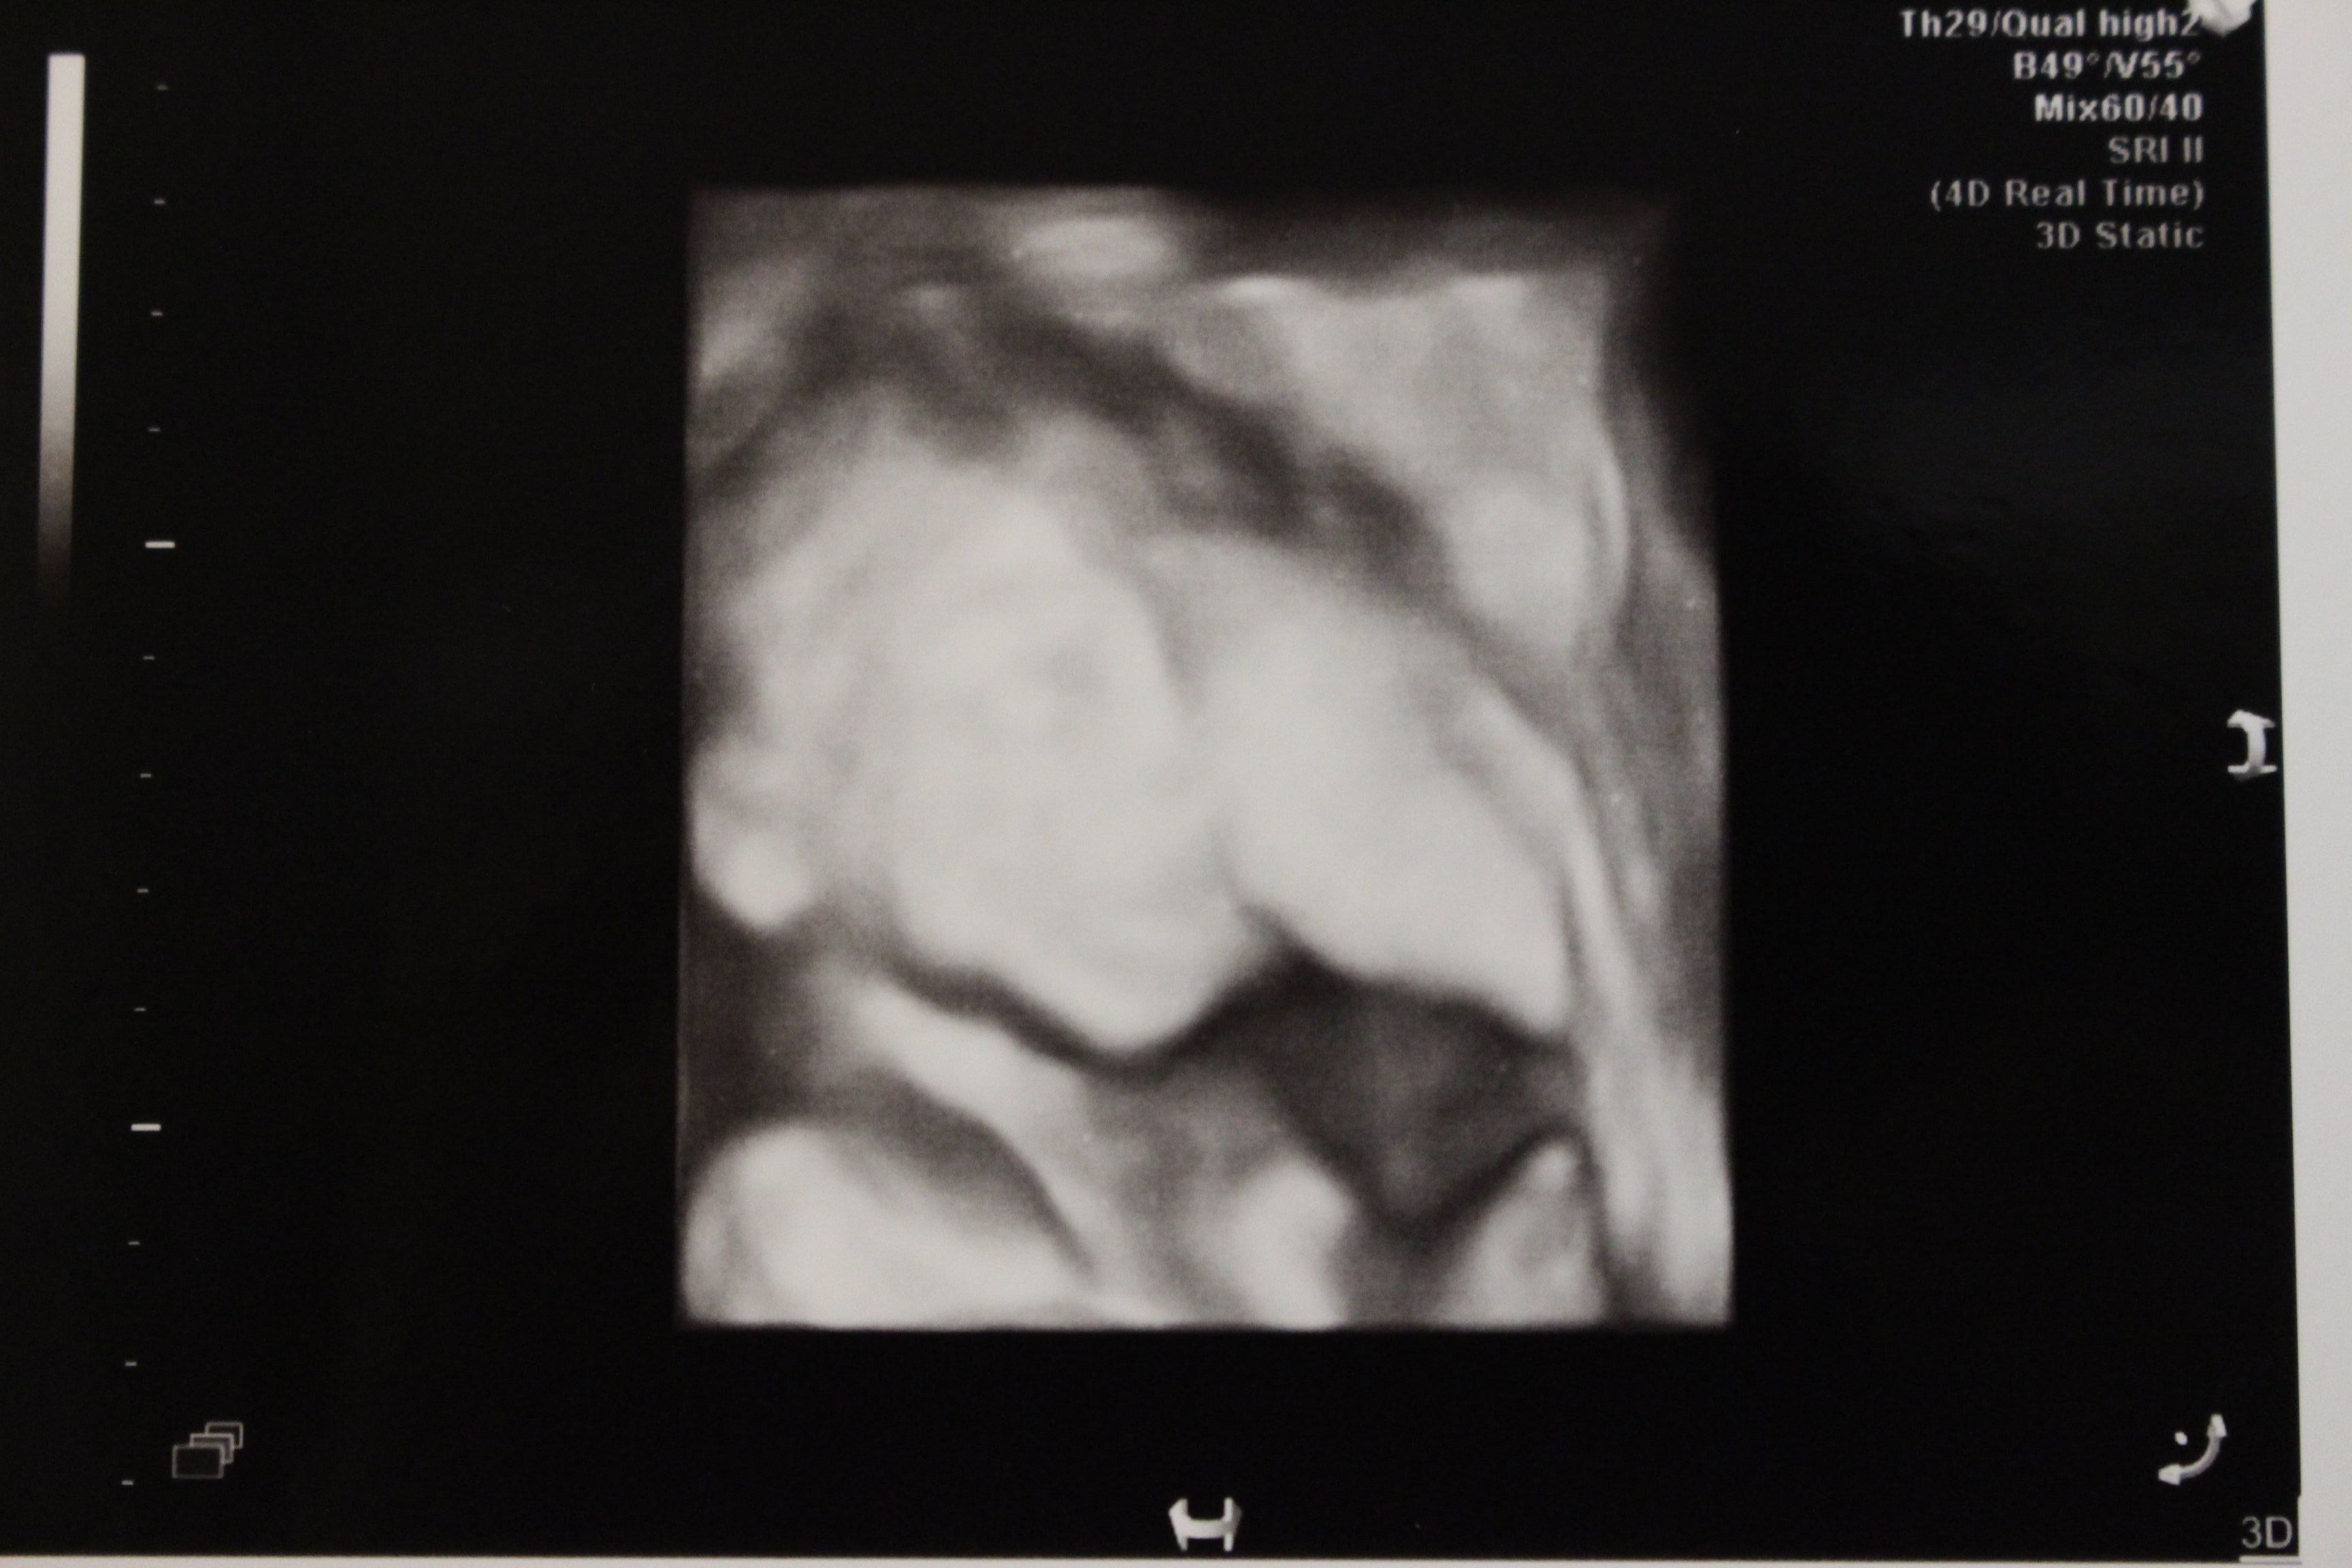

妊娠24週目の4Dエコー写真 (一部)

妊娠24週目4Dの一部画像。手で顔を隠すしぐさと、首にへその緒を巻いている様子が見えます。赤ちゃんの体重727g母体の体重60kg!つわりもおさまった頃で体重管理を意識し始めた時期です。この頃、母親学級で知り合った同じ産院で分娩予定のプレママが管理入院することになり、健診の帰りにお見舞いに行きました。